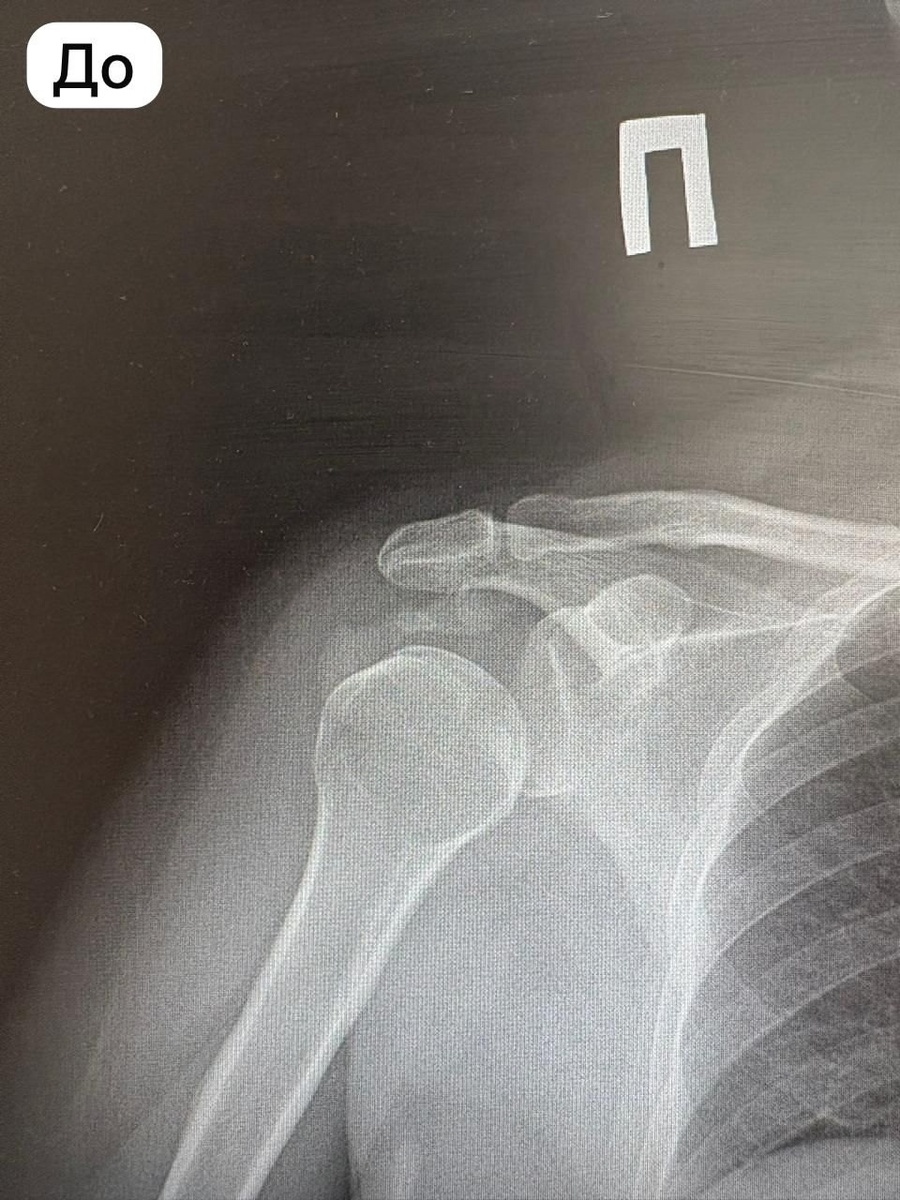

В Башкирии врачи без надрезов удалили отложения кальцината в плече

В городской клинической больнице №1 Стерлитамака впервые врачи инновационным методом удалили пациенту отложения кальцината плечевого сустава. Процедура называется барбатаж, пояснил главврач Ильшат Яппаров.

Врачи отделения травматологии и ортопедии через небольшие игольчатые проколы, без единого надреза, удалили кальциевые отложения объемом 2 см³. Тем самым избавили мужчину от болей и увеличили подвижность суставов.